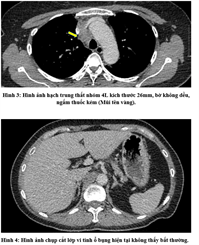

UNG THƯ BIỂU MÔ TẾ BÀO THẬN

Ung thư thận là loại ung thư thường gặp đứng thứ 14 trên toàn cầu, với hơn 430.000 ca mới được chẩn đoán vào năm 2020, và 434840 ca mắc trên toàn cầu vào năm 2022. Tỷ lệ mắc thay đổi theo khu vực địa lý, cao hơn ở châu Âu và Bắc Mỹ. Ung...